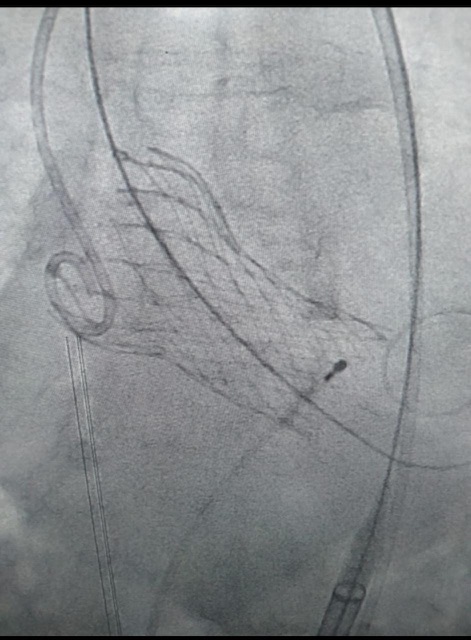

نجح أطباء مجمع الأقصر الطبي الدولي - المستشفى الدولي سابقا - بمدينة الأقصر ولأول مرة في صعيد مصر، في زراعة الصمام الأورطي عن طريق القسطرة التداخلية باستخدام تقنيه TAVI العالمية التي تجري دون جراحة قلب مفتوح أو تخدير، وتستغرق ما يقرب من 30 دقيقة على الأقل.

وأجرى أطباء المجمع الطبي الدولي زراعة الصمام الأورطي بنجاح في أقل من ساعة وخرجت المريضة بصحة جيدة بعد أقل من 24 ساعة تحت الملاحظة ومتابعة كافة العلامات الحيوية مع استعادة قدرتها على التنفس والحياة بصورة طبيعية.

وتستخدم لزراعة صمامات القلب والأوعية الدموية دون جراحة القلب المفتوح أو حتى التخدير وهي أهم المخاطر والموانع التي كان يقابلها كبار السن بالإضافة إلى تجنب شق الصدر جراحيا والحاجة إلى شهور من التعافي.

وتتم تلك التقنية في وقت قياسي قد يصل إلى أقل من ثلاثين دقيقة ويستطيع المريض بعدها مغادرة المستشفى في أقل من 24 ساعة ليعود إلى حياته الطبيعية السابقة لإصابته بأمراض القلب والصمام كما أنها تساعد علي تحسن كفاءه القلب بشكل كبير فقد مارس الكثير بعدها الرياضة والتمرن.